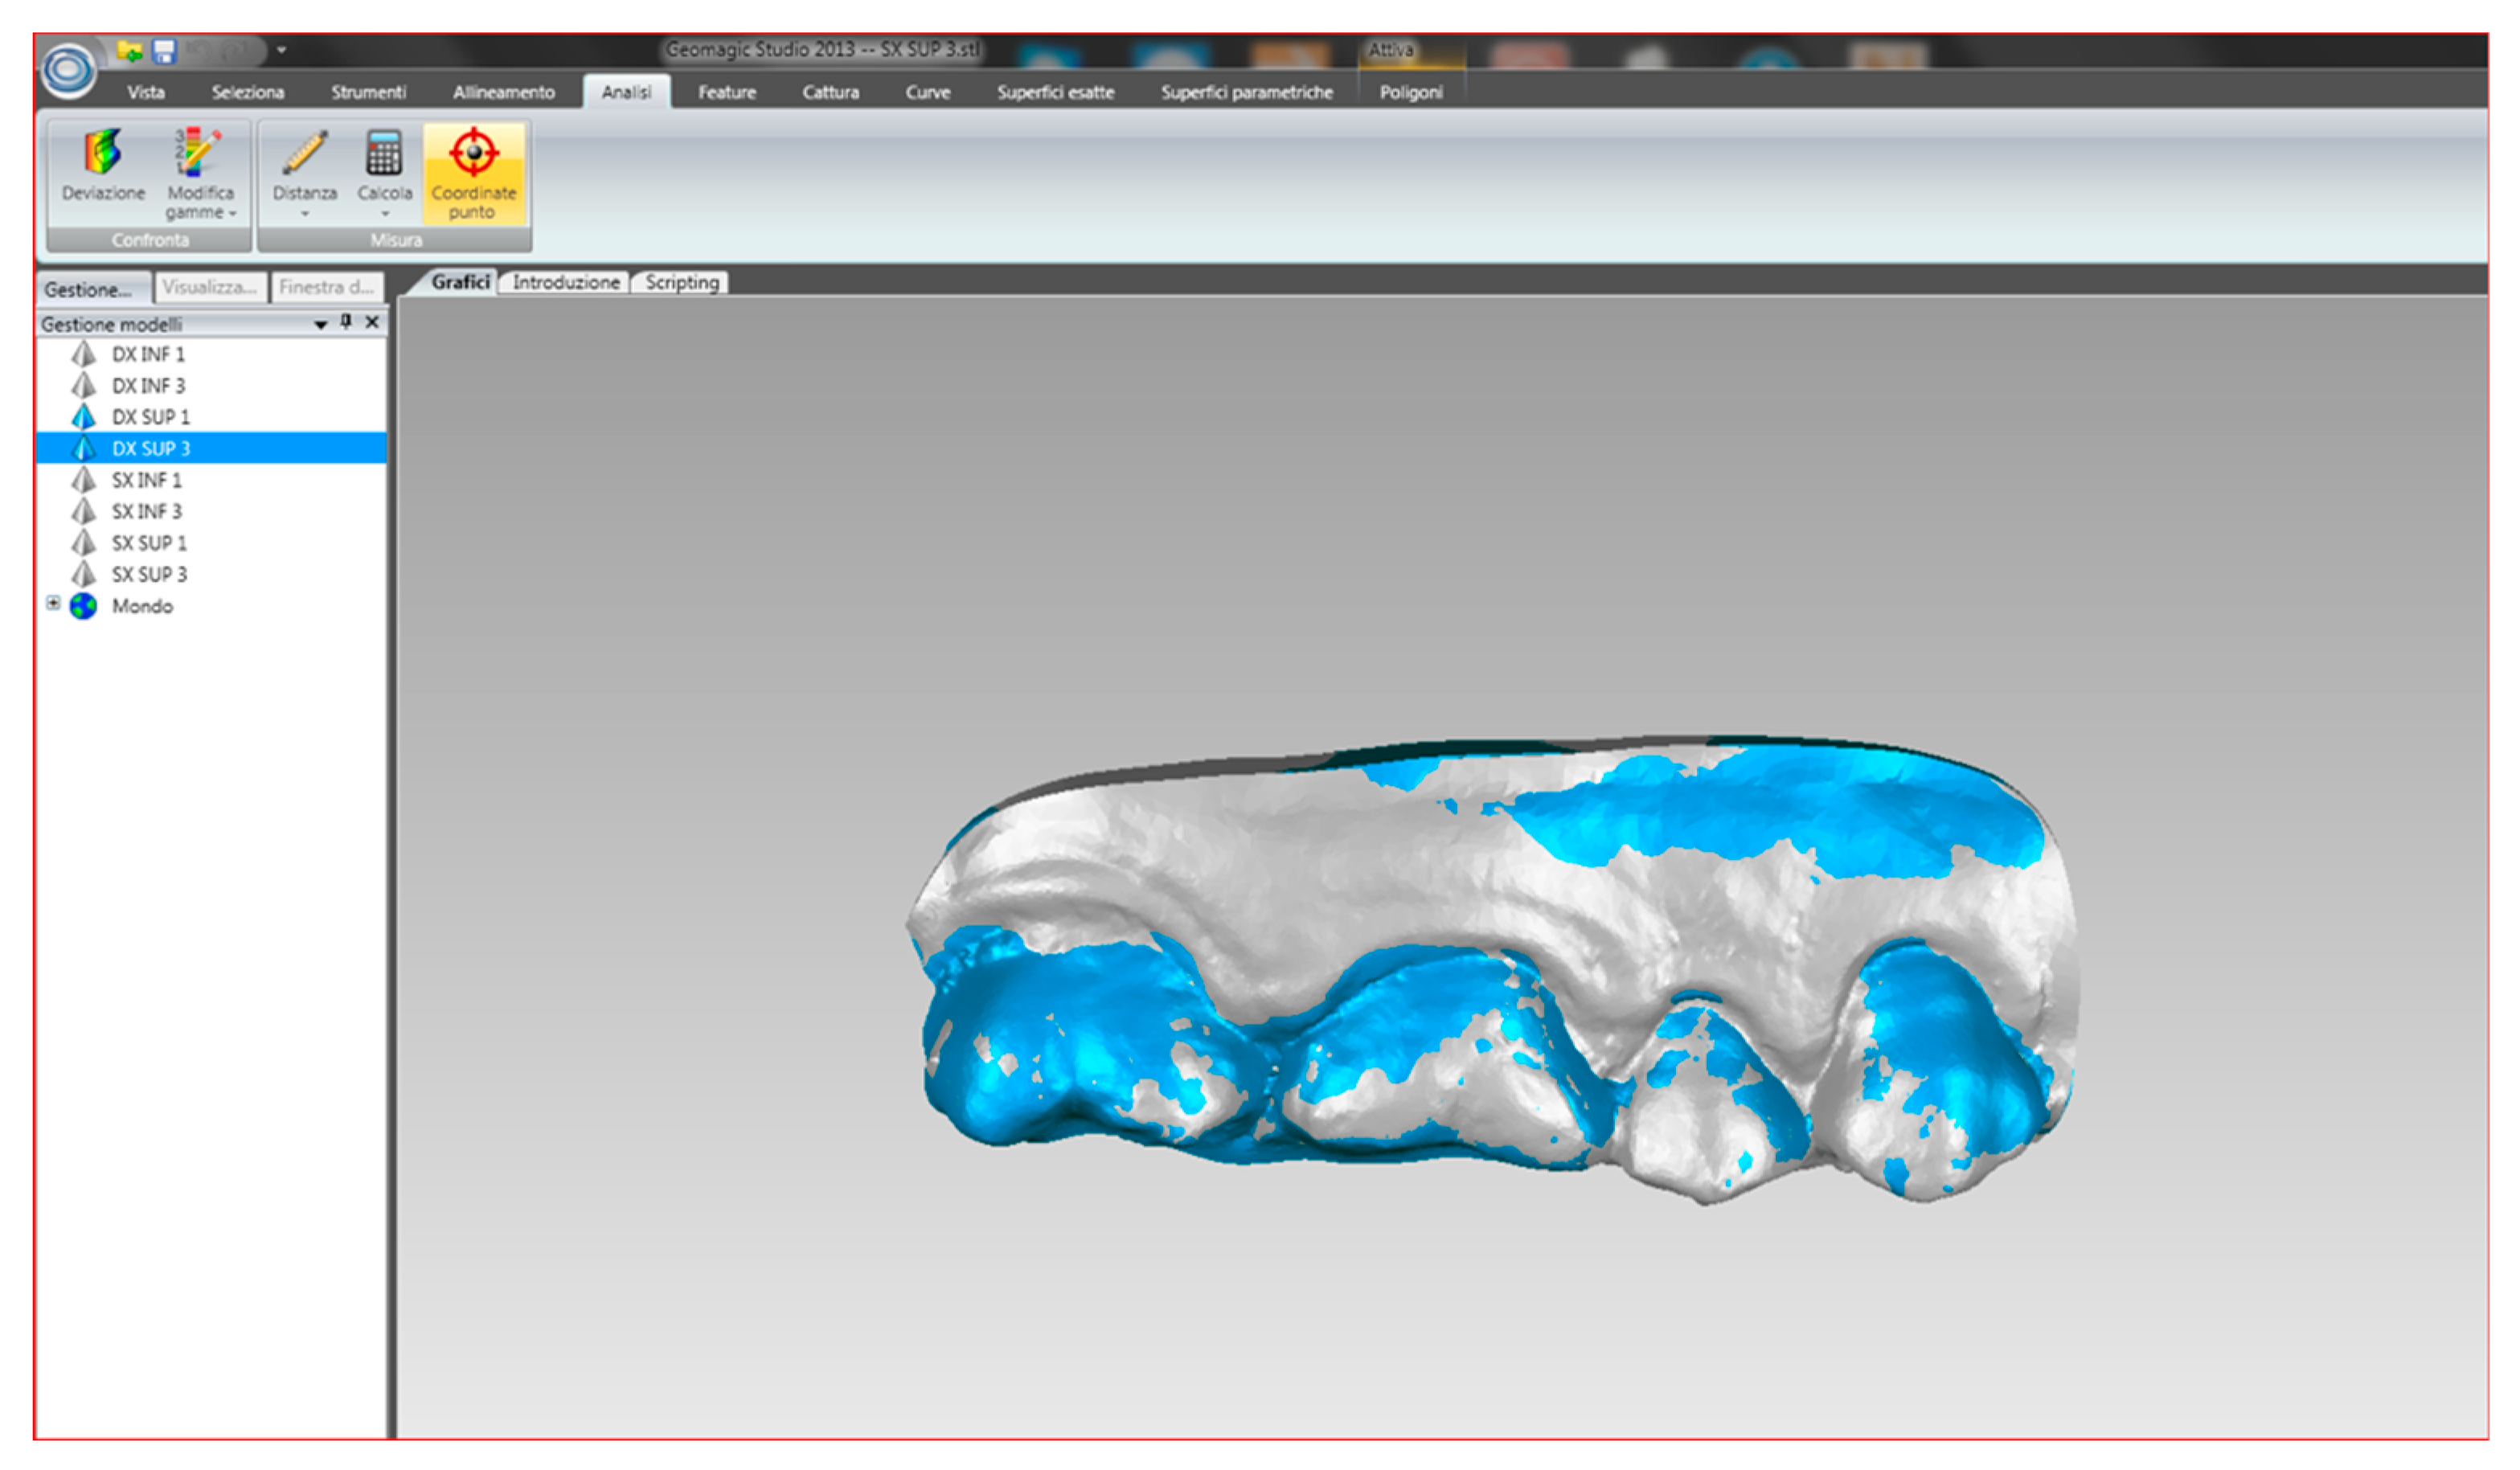

2.3. Procedure

- mandible

- maxilla

- buccal occlusal registration

- Partial scan of the arch: several teeth in the preparation area on the mandible and maxilla, and a buccal occlusal registration.

- Complete scan of the arch: maxilla, mandible and buccal occlusal registration.

2.5. Treatment of the Collected Data